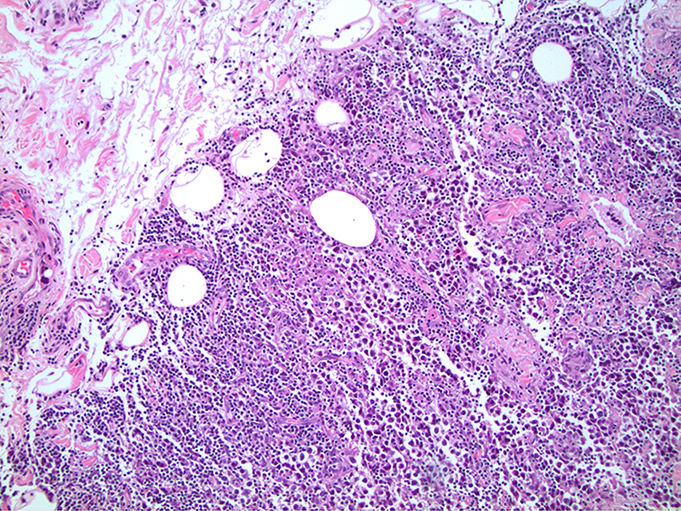

Microscopic (histologic) images

Board review style question #1

In a postpubertal testicular germ cell tumor, lymphovascular (shown above), hilar fat, epididymal and tunica vaginalis invasion are all a part of which pT category?

Board review style answer #1

D. pT2. Lymphovascular, hilar fat, epididymal and tunica vaginalis invasion are all a part of the pT2 category for testicular germ cell tumors. Lymphovascular invasion by embryonal carcinoma is shown in the image.

Comment Here Reference: